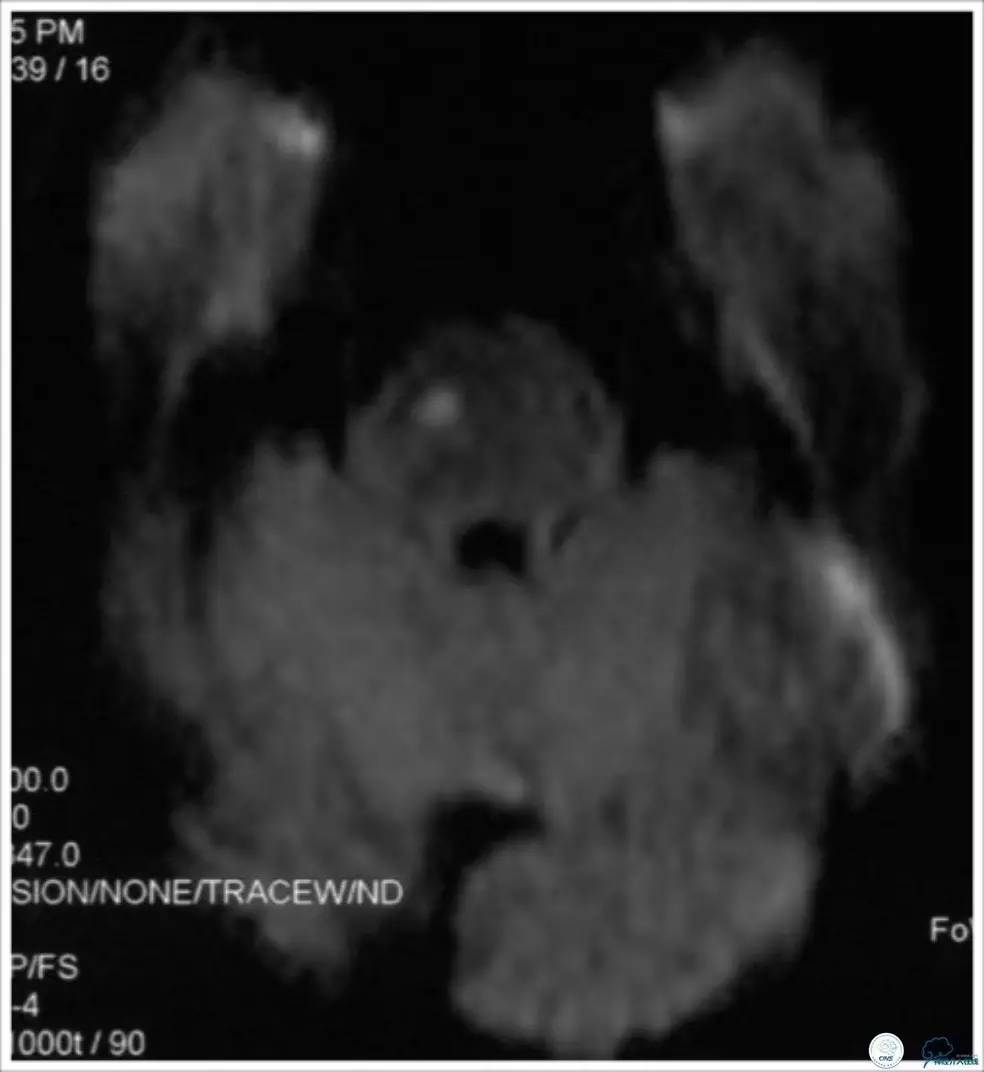

患者,男性,52岁,主因“反复头晕10月”入院。10个月前无明显诱因出现头晕,伴视物旋转,治疗后好转(具体不详)。7个月前头晕再次发作,伴视物旋转、视物成双、耳鸣、恶心呕吐,反复发作数周后好转(每周发作4-5次)。 5个月前上述症状再次反复,伴行走不稳。患者每次症状持续数分钟到数小时不等。至当地医院就诊,查头颅MR示右侧脑桥亚急性梗死(图2)。

图2